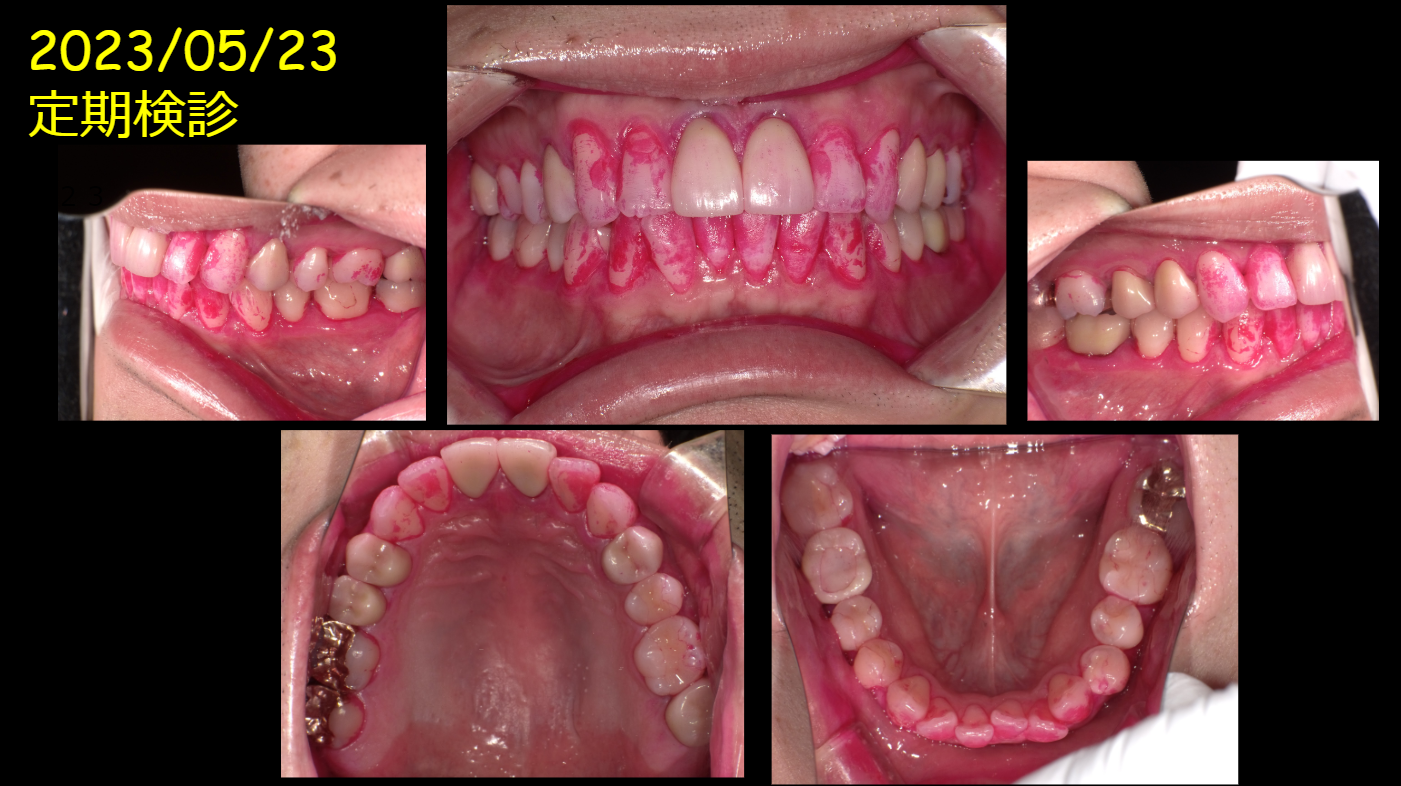

上記の写真の患者さんには

[せっかく治したのにどうしてもっとよく磨かないのですか?]

【これじゃ、また悪くなってしまいますよ!】

っと熱心な衛生士さんならばきっと伝える事でしょう!